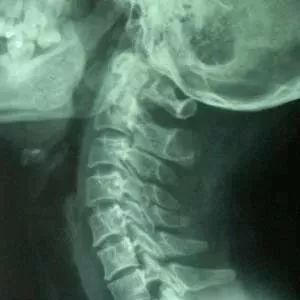

不是我自己发现的,是大夫发现的,但奇葩的是不是内科大夫、不是妇科大夫,发现我怀孕的是个骨科大夫。

那是2017年上半年,一向睡眠质量爆好有倒头秒睡雷打不醒之特异功能的我忽然晚上睡不好了,翻来覆去的觉得怎么睡脖子都不舒服,白天整个人感觉胀胀晕晕的,反而想睡。我对怀孕没有一点警觉,对长期办公室伏案工作导致颈椎问题非常担心。觉得自己的症状很像,脖子不舒服,颈椎问题导致头昏脑胀,继而导致晚上睡不好,晚上睡不好又导致我白天只想睡觉。

对!没错,就是这样,破案了,我得去看看我的颈椎!

然后,我就做了人生至今最大的死,去医院在没有任何防护下拍了张X光片。现在坐办公室的颈椎太容易不好了,我要保护好我的颈椎呀(当时脑子一根筋抽得厉害)

然而万幸,在我脑袋抽得厉害的情况下,为图方便我去的是公司附近的一家中医院。

能说什么呢,感谢中医,感谢我国传统医学,感谢当时接诊医生的警觉。看我片子没问题,又听我絮絮叨叨的说晚上睡不好脖子不舒服,她灵光一闪,拉过我的手,给我把了个脉。

正规医院正经中医真的能把脉啊!骨科医生这抓腕子一把,就把出了喜脉。当时气氛有点慌,因为孕妇应该要避免辐射的而我刚去拍了两张片。接诊的大夫让旁边的另一位骨科大夫拉过我的手再次把脉确认,结果很沉痛啊,两骨科大夫双双表示,我的脉相确实滑(喜脉),让我回去赶紧找医院看妇产科。

好吧,现在我宝贵的颈椎已经不重要了,拍片辐射对胎儿有没有影响才是重点。回去一通查,肠子都悔青了。好在妇幼院的医生确认表示早期这点微量辐射没影响,这才吃了定心丸开始了我的怀孕之旅……